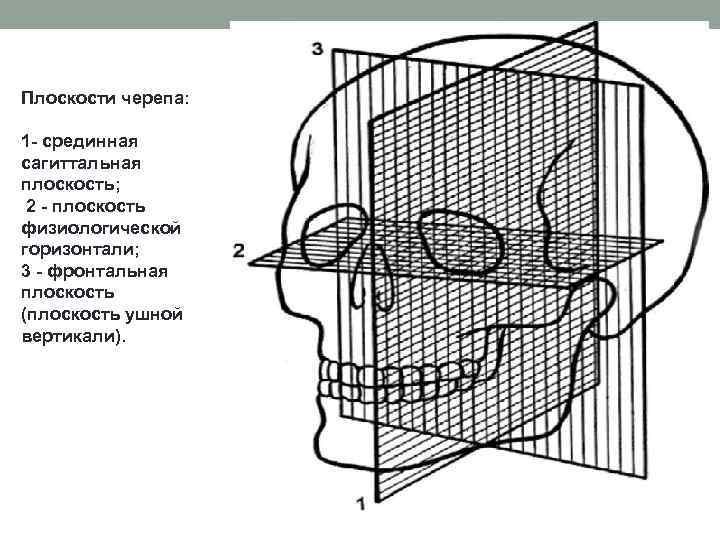

Анатомические изображения срединной сагиттальной линии черепа